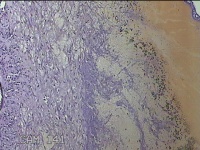

左卵巢囊肿

性别

女

年龄

47岁

临床诊断

左附件囊肿

一般病史

不规则阴道流血20余天。

标本名称

大体所见

灰白暗红色囊壁样组织4.3x1.3x0.3cm一块,表面光滑,因已切开,囊内容物已流失,囊壁厚0.1cm。

良性病变。